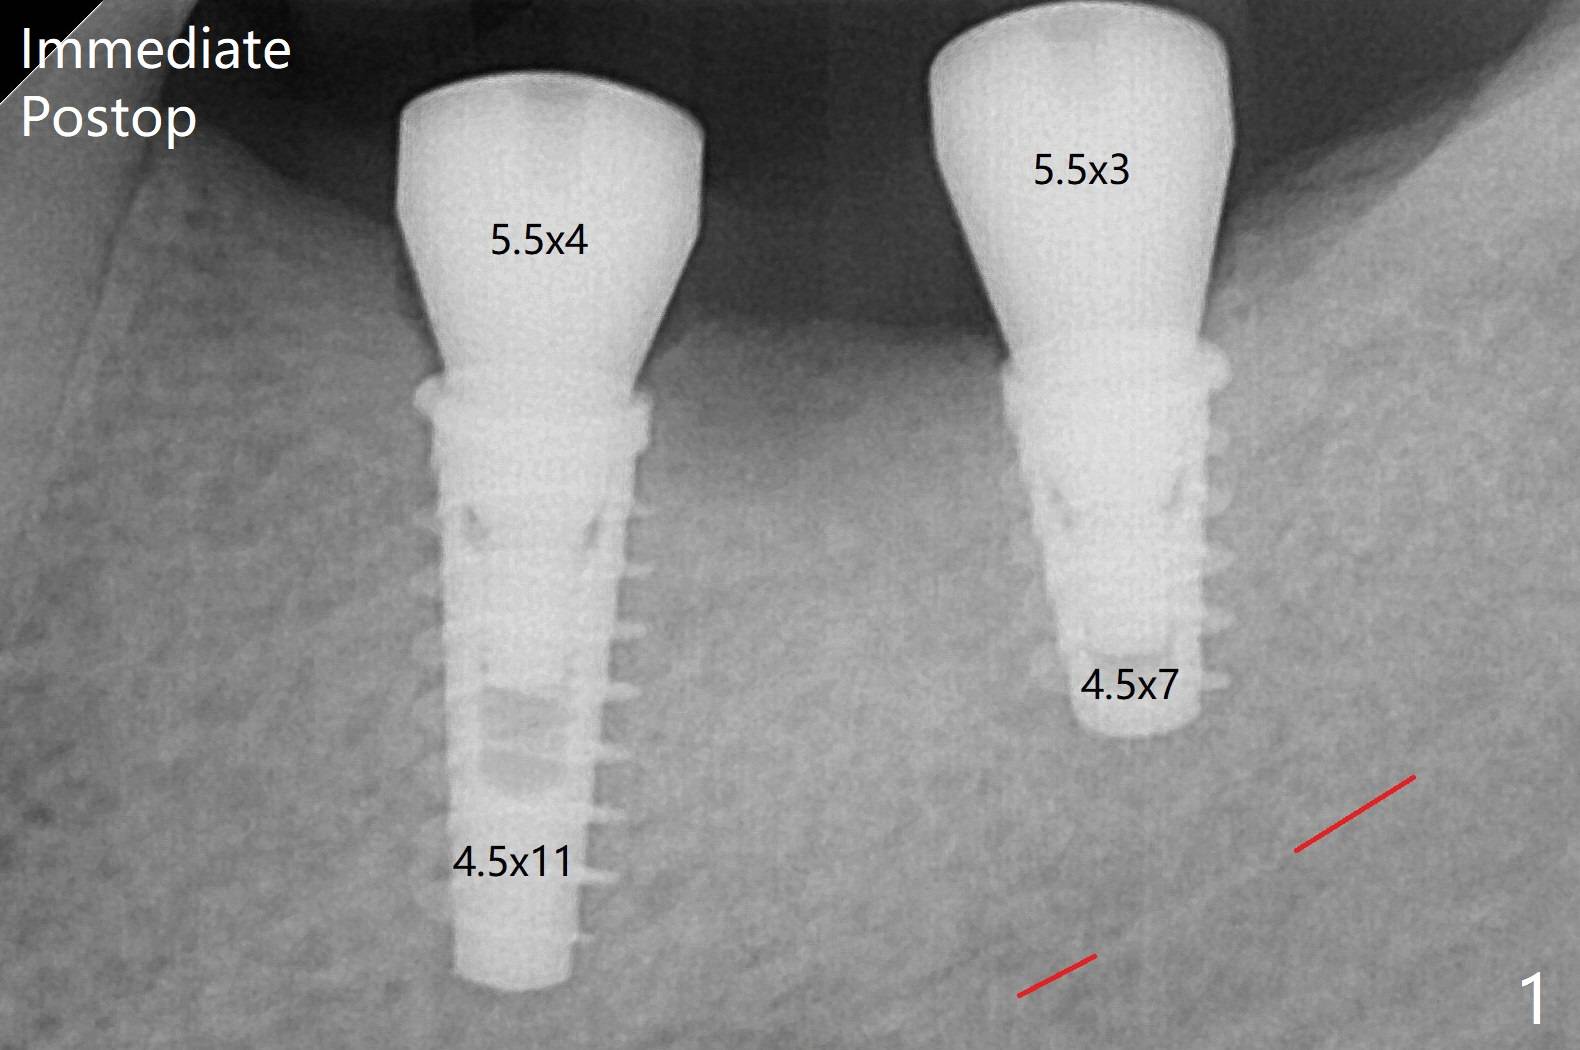

There is crestal bone loss in 3 months (Fig.2, as compared to Fig.1).  Since there is more space apical to the pair abutment at #19 than that at #18, incomplete abutment seating is suspected at #19.  More X-ray will be taken.  In fact, it is not necessary.   The space differential is also noted with healing abutments in Fig.1.  The implant at #18 tilts lingually, which accounts for indistinct threads at #18 and 19.